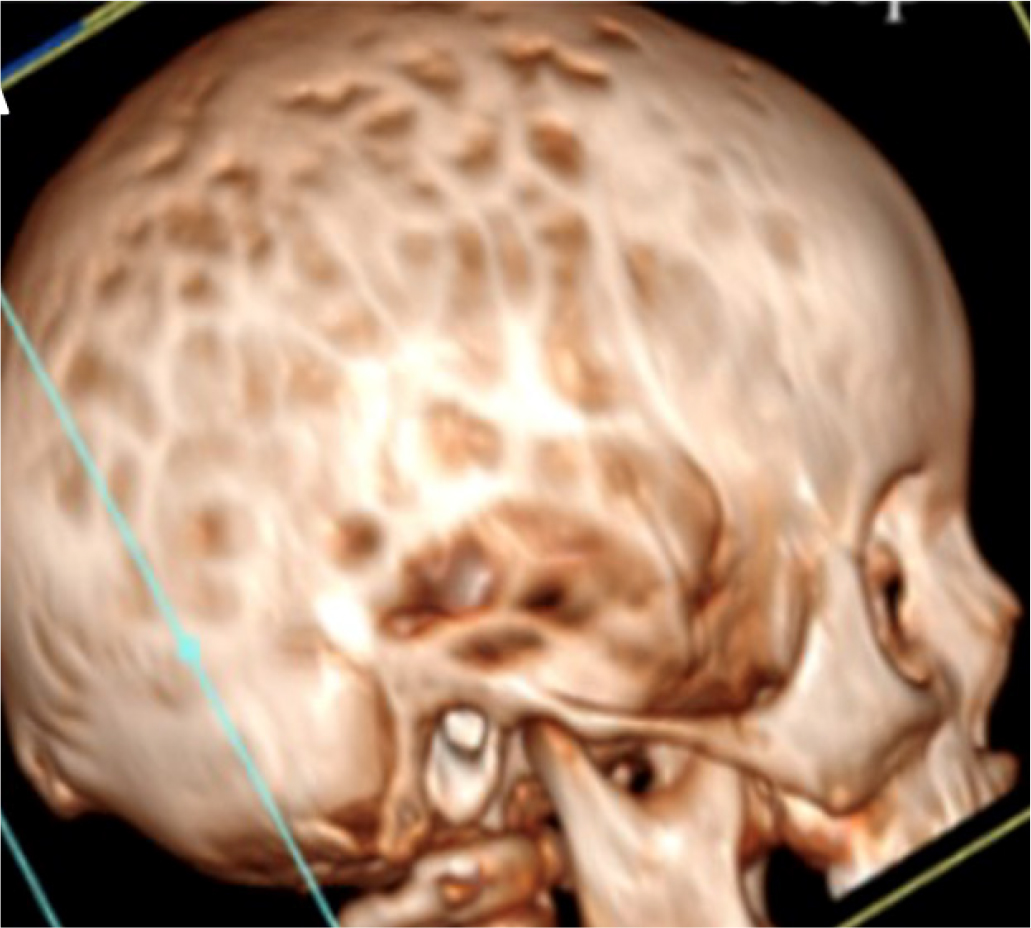

Molecular analysis of PHEX revealed the nonsense variation C.2104 C>T (p.R702X) in both the patient and his mother. The child promptly started treatment with phosphate salts and calcitriol. At 30 months, turricephaly, microcephaly, and prominence of the sagittal and coronal sutures were observed. Some episodes of headache associated with vomiting were reported and he was referred to our center. Computerized tomography (CT) showed pansutural craniosynostosis, enlarged fingerprints (Fig. 2), and ectasia of the cerebellar tonsils. Fundus oculi examination revealed papilledema and MRI of the brain showed tortuous optic nerves. The child was referred for neurosurgical evaluation.

Fig. 2 - Cranial computed tomography image of case 2 showing pansutural craniosynostosis with enlarged fingerprints and ectasia of the cerebellar tonsils.